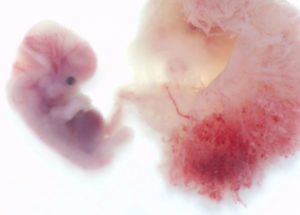

В начале беременности плод растет буквально «не по дням, а по часам». На пятой неделе, он уже успел превратиться из шарообразного плодного яйца в эмбрион, напоминающий своим внешним видом головастика.

Если срок беременности пять недель, то размер плода сравним с зернышком риса. Его вес немногим более одного грамма, а размер – около трех миллиметров.

Если срок беременности уже пять недель, то на месте шарообразного плодного яйца уже успел сформироваться эмбрион. Внешне он похож на диск, разделенный полоской пополам. Эта полоска – ось симметрии тела будущего человечка, то есть, будущий позвоночник. На этом сроке плод уже имеет зачатки некоторых внутренних органов. У него начинают формироваться системы дыхания и пищеварения.

Если контур плодного яйца напоминал шарик, то плод на пятой неделе можно сравнить с полумесяцем или буквой С. У него уже можно различить место, где будет формироваться голова.

Размер ребёнка составляет 4-5 мм. У эмбриона начинают формироваться органы. Изо дня в день развитие усложняется. В начале недели у ребёнка сформируется нервная трубка — основа для процесса развития центральной нервной системы. Она находится по длине всего организма эмбриона и даёт возможность развиться головному и спинному мозгу.

На 5 неделе беременности организм будущего ребенка продолжает свое бурное развитие. В беспорядочном, казалось бы, делении клеток появляется определенная система и уже можно под микроскопом различить зачатки отдельных частей тела.

Ваш малыш теперь напоминает головастика. Поразительно, но у него уже начинают формироваться реагирующие на свет глазки и ноздри, а также развивается сердечко. Кстати, если вы ждете мальчишку, то у него уже закладываются зачатки семенников, практически сразу начинающие производить тестостерон. Ваши яичники продолжают вырабатывать гормон прогестерон, который поддерживает беременность.